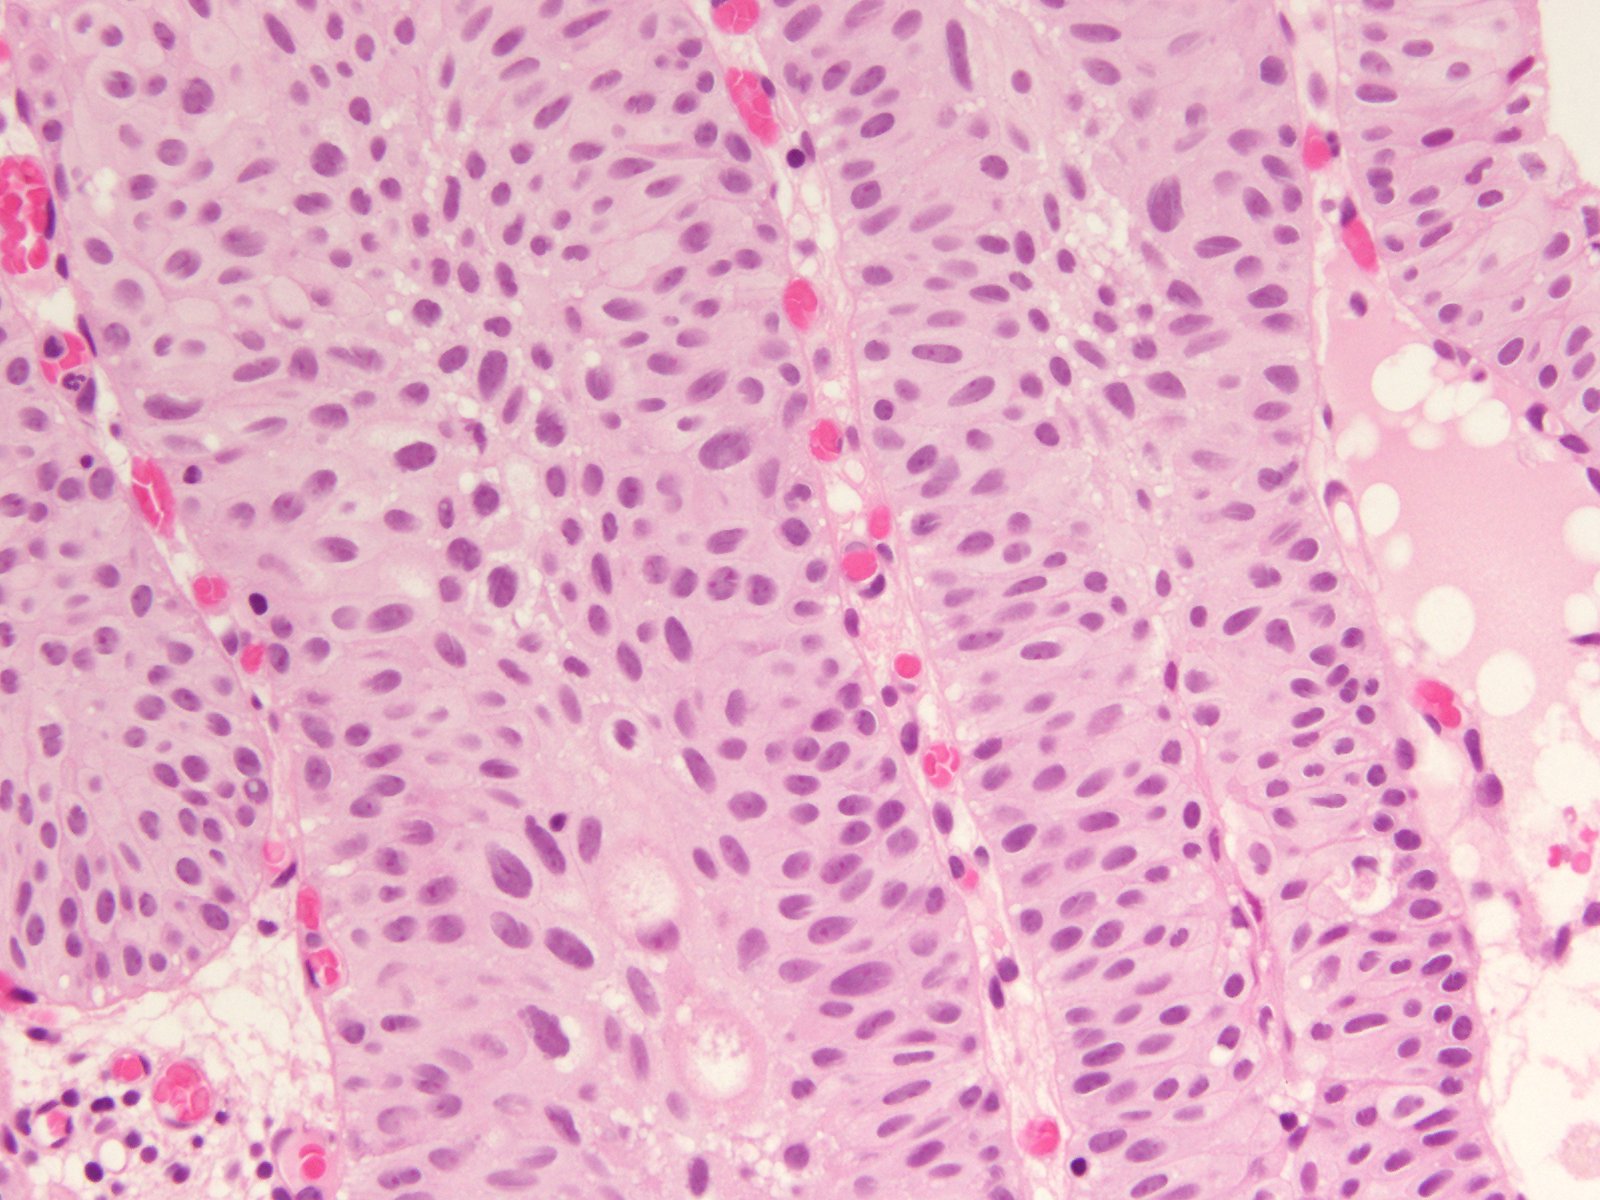

Case ID: 407

Consensus grade: Low-grade papillary urothelial carcinoma (LG-PUC)

Case description (by case creator):

57 y/o. Bladder tumor.